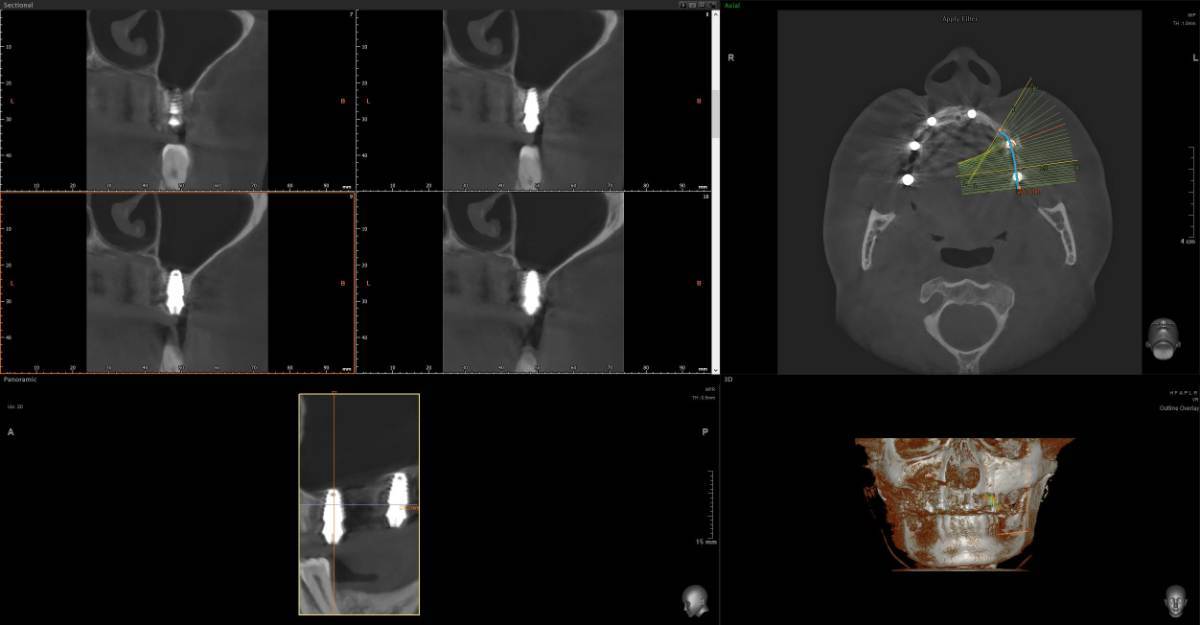

Всем привет, коллеги! 14 лет, терапевты ставят трещину по КТ (снимков до, к сожалению нет, косяк, каюсь). чуть сепарировав зуб и глянув на зуб под отлетевшим куском пломбы трещина "подтвердилась". Кейс на фото. Из интересного - маленький реколл в 1.5 года и спокойное перемещение зуба брекетами!